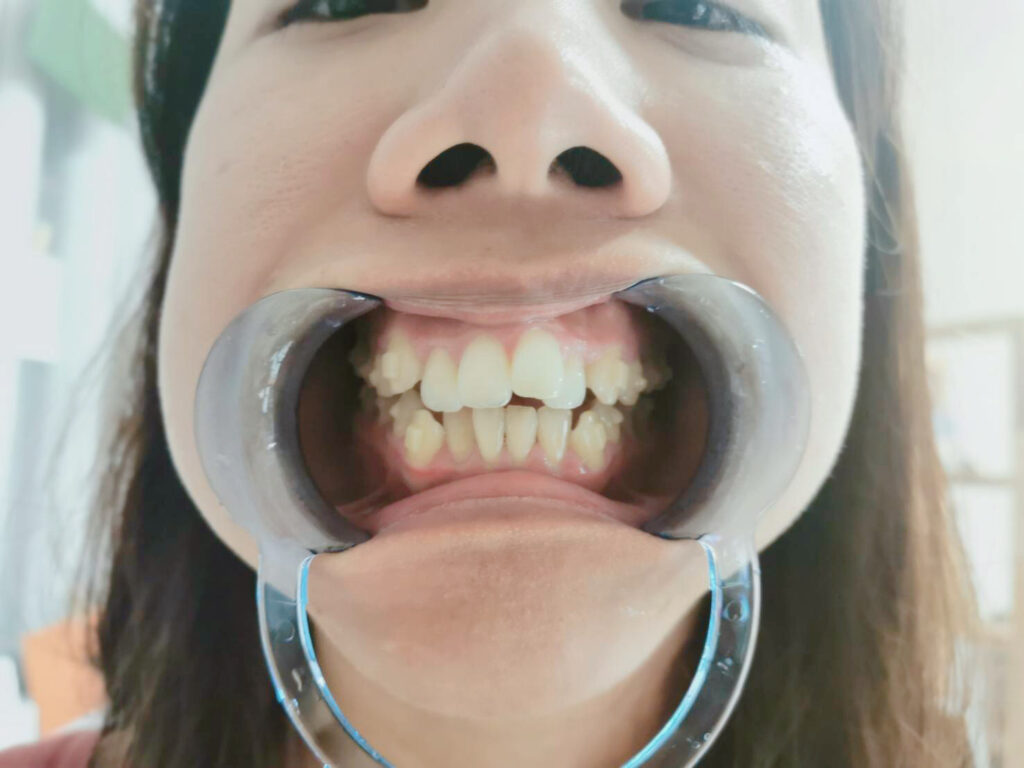

下排牙齒:排列整齊不再凌亂

Before:我的下排牙齒相對上排還是整齊很多,但依然有齒列不整的問題,犬齒完全跟大家不在同一個水平線。因為齒列不整,一些歪七扭八的縫縫會無法清潔乾淨,導致牙結石等牙周問題。

After:SOV隱形矯正過後下排牙齒也很快就整齊畫一了,在牙齒矯正的過程中我更養成良好的潔牙習慣,除了刷牙之外,牙線跟沖牙機也是我每天都會使用的工具,牙周問題更因此消失,每次回診都被聰哥稱讚照顧得很好!

咬合部分:牙齒開咬矯正問題

Before:看看這個牙齒矯正前根本咬不斷任何東西的咬合XD